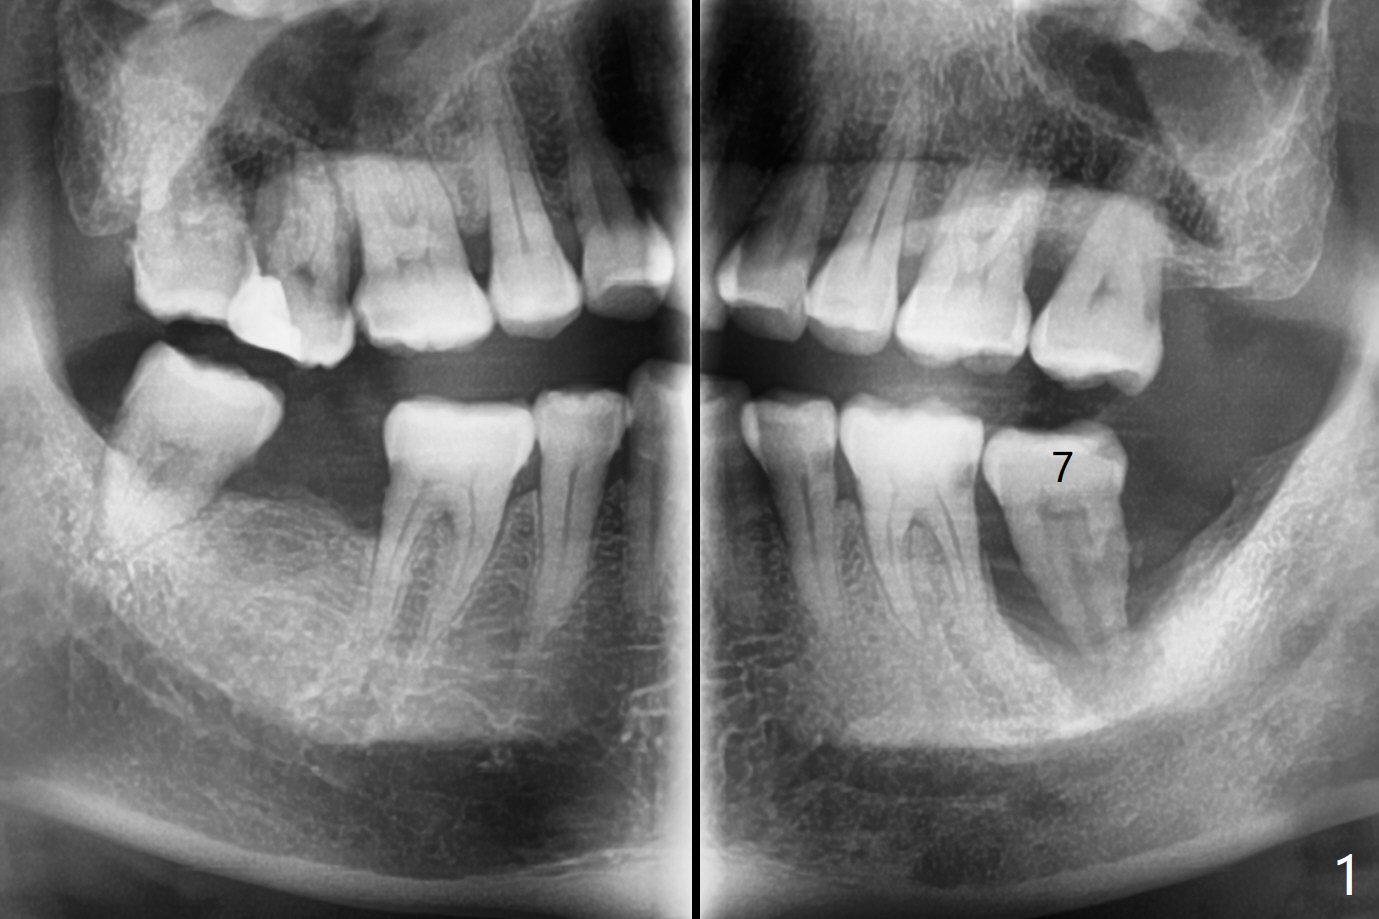

52岁男要求拔除松动左下7(图一,二),同意植骨,我们需要注意什么?我一般在类似情况下,使用浸润麻醉,但是今天改用block anesthesia,加浸润麻醉,直接将局麻药注射于牙龈,疼痛和出血控制好(图三:G(含有肾上腺素纱布)),麻醉方面有什么缺点?我不喜欢block anesthesia,万一碰到神经,麻醉深,病人不会给提醒。牙槽窝近中舌侧远中骨壁肉芽组织彻底清除;由于视野不好,切开(图四),牙槽窝底部*是软的,敢去除吗?其实我第一次向软组织投降,不敢去除,好像挺容易出血,接着敢植骨吗?其实植入粘性骨粉(皮质骨),术后CT检查表明遗留肉芽组织(图五:*),大约4毫米厚(图六),病人身体现在可忙乎了。覆盖PRF膜和不可吸收膜各一张,4-0 PTFE缝合,开口基本关闭,最后使用树脂敷料。